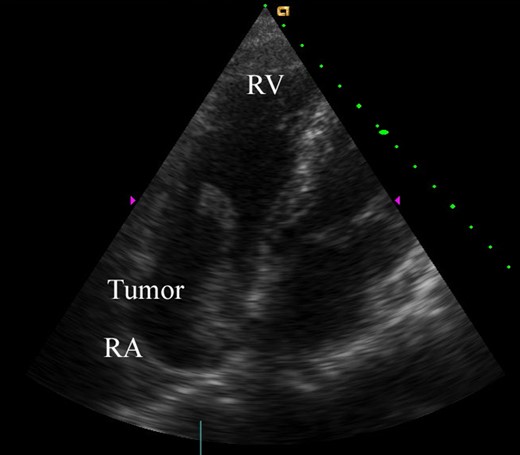

A 74-year-old male patient was referred to our hospital for the treatment of a right atrial tumor. He had experienced the sudden onset of dyspnea and had gone to another hospital. There, transthoracic echocardiography revealed the right atrial tumor. After his transfer to our hospital, transthoracic echocardiography was performed again. The right atrial tumor, which adhered to the interatrial septum, had a tail-like surface projection. The tumor projection was mobile and prolapsed into the right ventricle during diastole (Fig. 1). In addition, the right cardiac cavities were dilated and the estimated right ventricle pressure was 63 mmHg, which suggested the presence of moderate pulmonary hypertension. Subsequently, computed tomography (CT) showed that the left pulmonary artery was occluded by a large embolus (Fig. 2). Because the embolus formed acute angles with the vessel wall, acute pulmonary embolism was highly suspected. We performed an emergency surgery for the removal of both the right atrial tumor and the embolus in the left pulmonary artery.

Preoperative transthoracic echocardiography. The right atrial tumor (40 × 20 mm) originated from the interatrial septum. The tumor had a tail-like surface projection, which prolapsed into the right ventricle during diastole. RV, right ventricle; RA, right atrium.